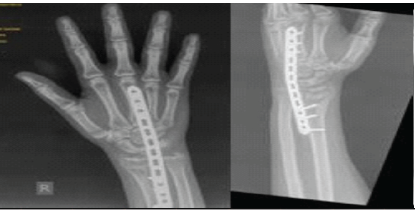

A Case Series of Functional and Radiological Outcome of Comminuted Distal Radius Fractures Treated with Bridging External Fixator with Optional Percutaneous K-wires

Subramanya Gandhi , Mohamed Safiullah , Vijay Narasimman Reddy , Ashin khan , Mervin Rosario P M